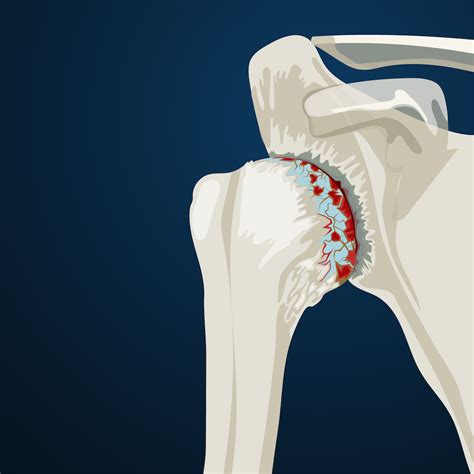

The shoulder joint is composed of the humeral head (the ball) and the glenoid (the socket). When the smooth cartilage that cushions these bones wears away, the bones begin to rub against each other, causing the inflammation and stiffness we recognize as arthritis. While age is the most common factor for osteoarthritis, other conditions like rheumatoid arthritis involve the body’s immune system attacking the joint lining. Regardless of the type, seeking early Arthritis In Shoulder Treatments is essential to prevent further degradation of the joint structure.